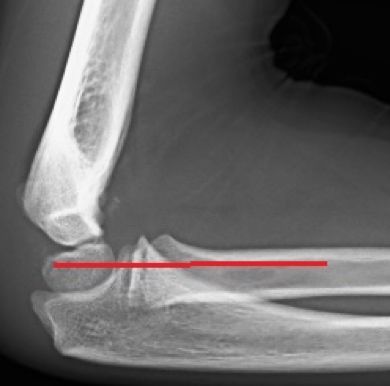

- El radio se dirige al capitelum en todas las proyecciones: cuando esto no ocurre, se debe sospechar una fractura del cóndilo lateral, una fractura del cuello del radio, una fractura-luxación de Monteggia o equivalente o una luxación de codo (Figura 4).